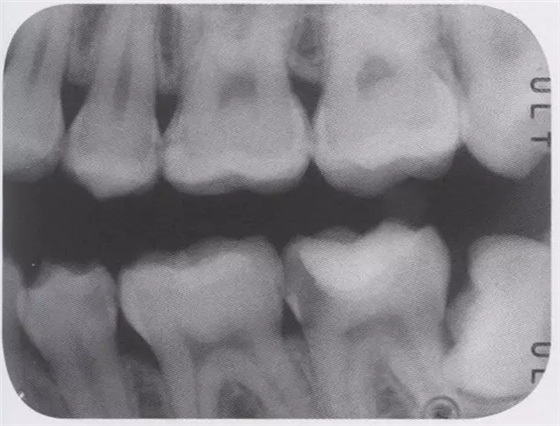

圖3 全瓷嵌體的修復(右56)。鄰接面產生齲齒的情況(上段,中段左),去除齲齒,并佩戴嵌體(下端)。